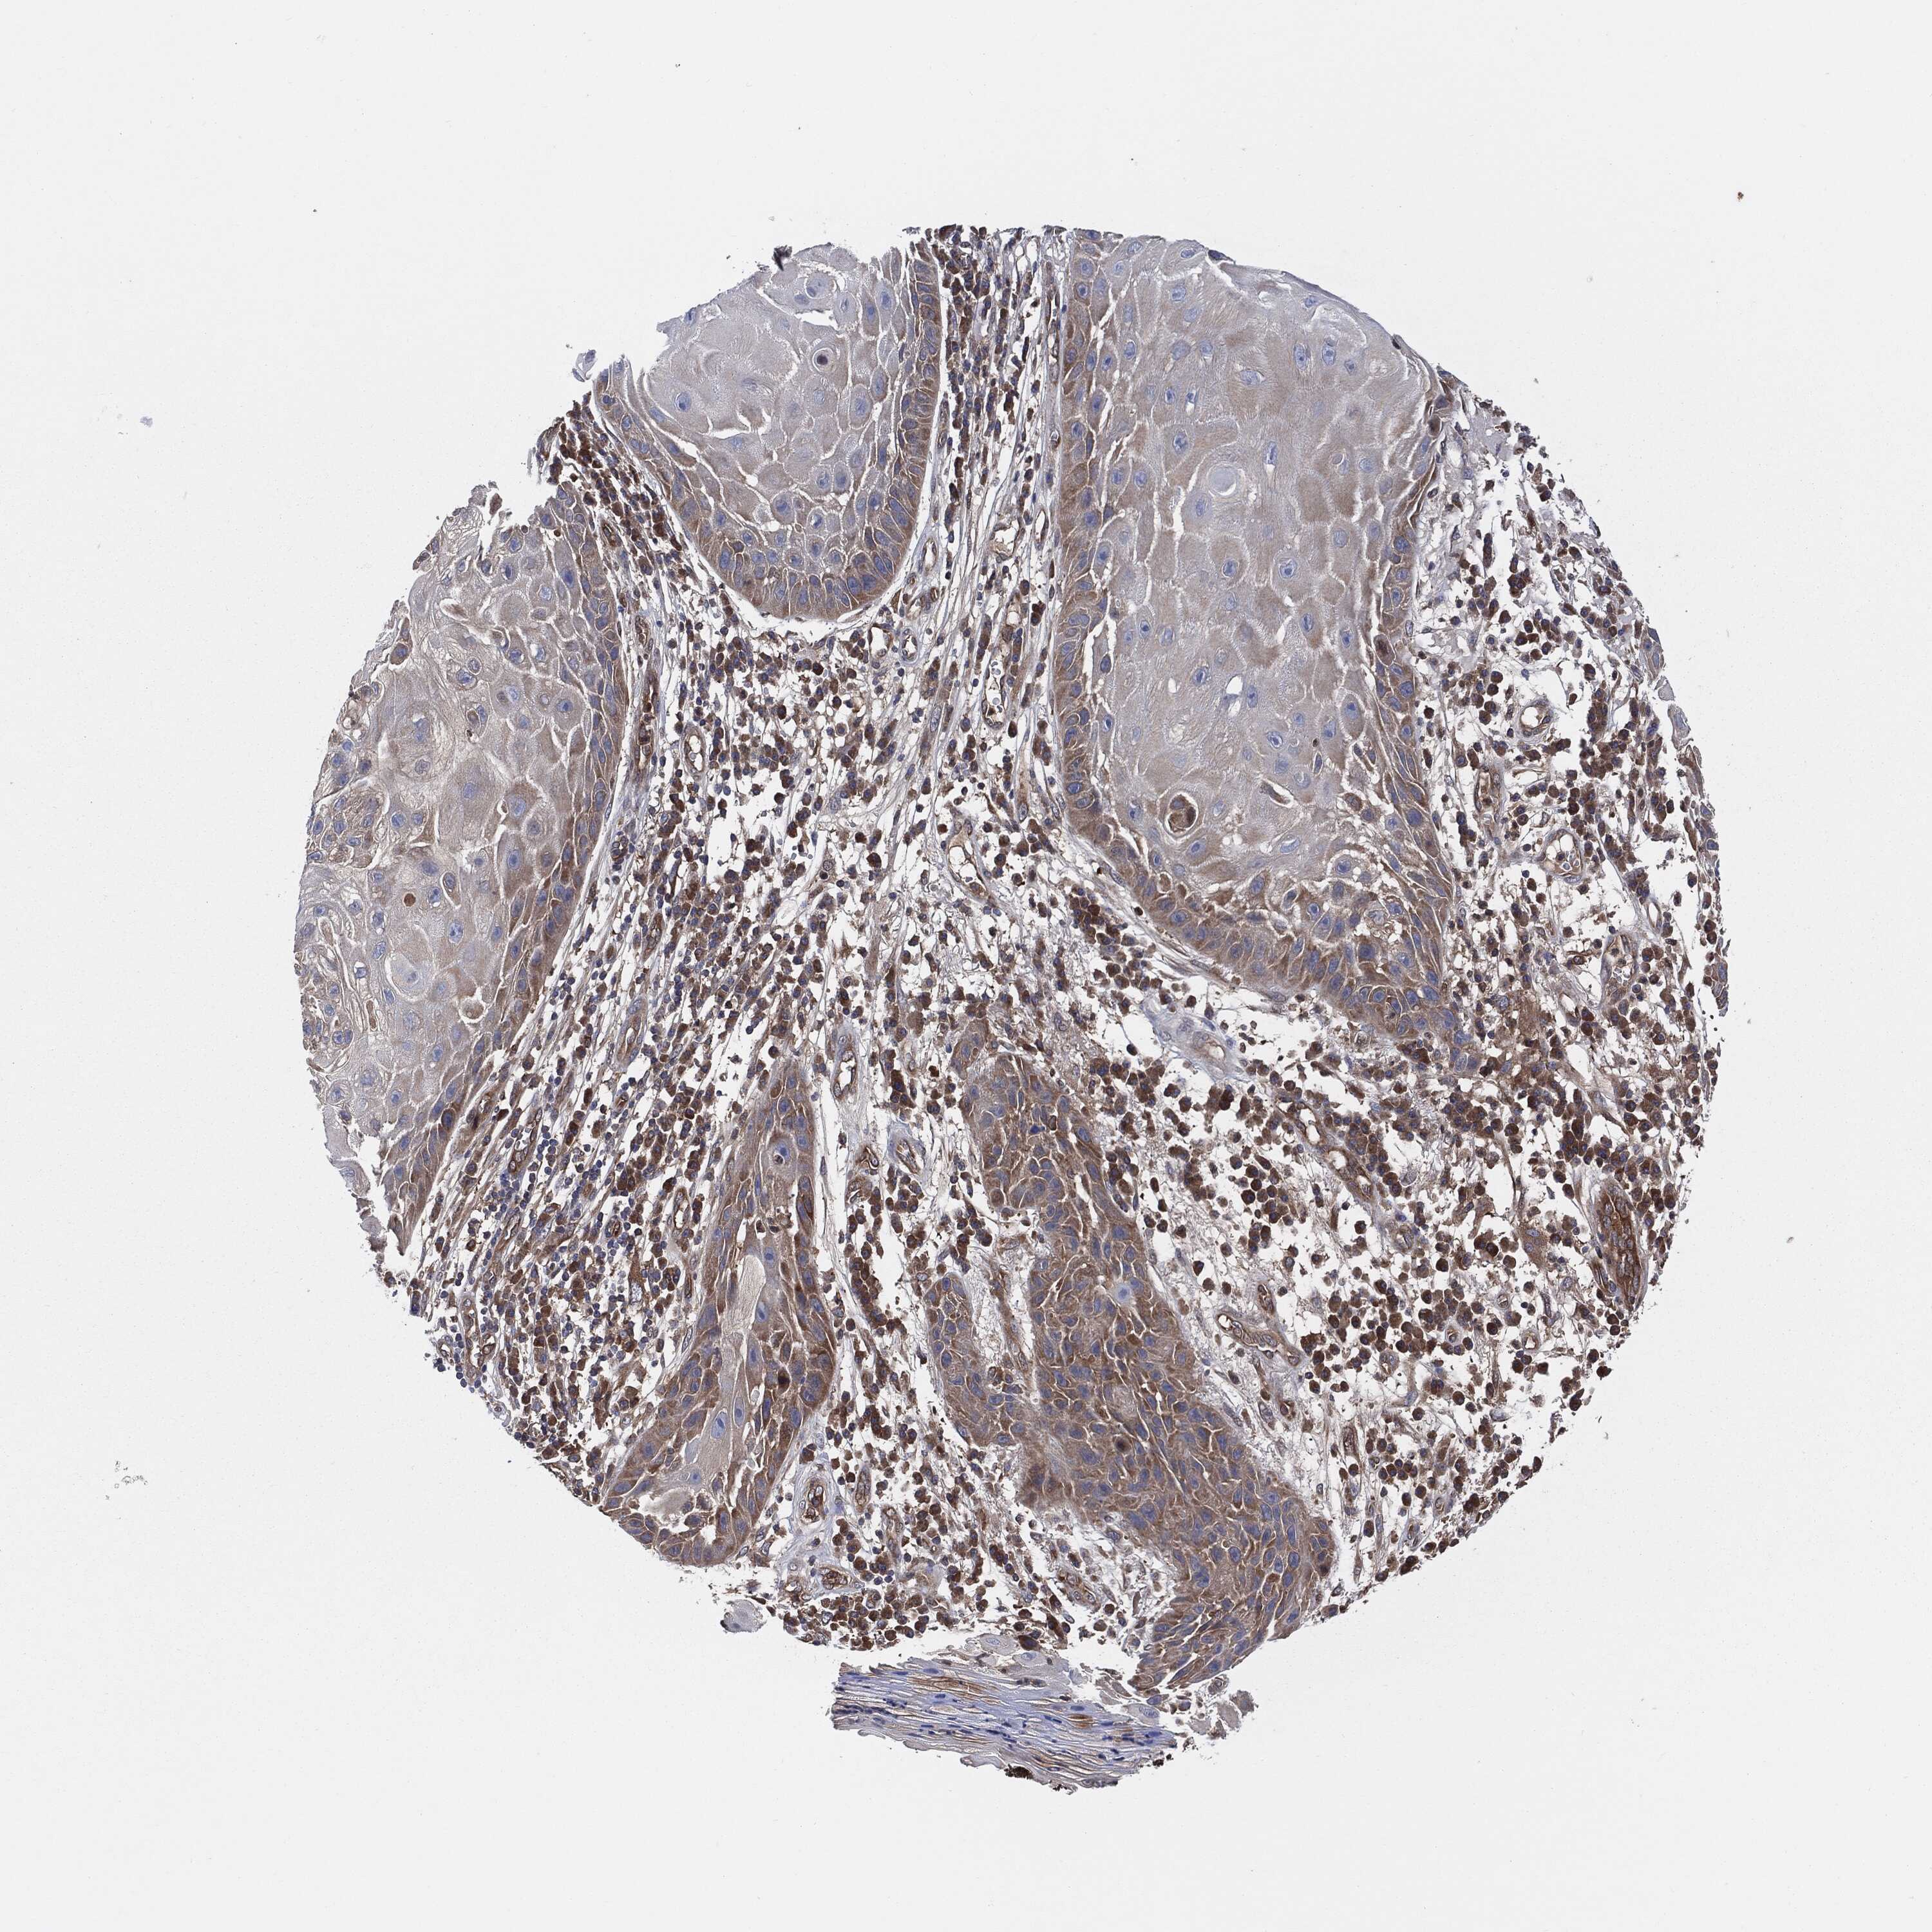

SKIN CANCER - Protein expressioni

A mouse-over function shows sample information and annotation data. Click on an image to view it in a full screen mode. Samples can be filtered based on level of antibody staining by selecting one or several of the following categories: high, medium, low and not detected. The assay and annotation is described here.

Antibody stainingi

Antibody staining in the annotated cell types in the current human tissue is reported as not detected, low, medium, or high, based on conventional immunohistochemistry profiling in selected tissues. This score is based on the combination of the staining intensity and fraction of stained cells.

Each image is clickable and will lead to virtual microscopy that enables deeper exploration of all samples and also displays staining intensity scores, fraction scores and subcellular localization as well as patient and tissue information for each sample.

HPA030419

HPA030420

HPA030422

CAB025196

CAB080286

CAB080287

Staining

High

Medium

Low

Not detected

Intensity

Strong

Moderate

Weak

Negative

Quantity

>75%

75%-25%

<25%

None

Location

Nuclear

Cytoplasmic/membranous

Cytoplasmic/membranous,nuclear

Basal cell carcinoma

Squamous cell carcinoma, NOS

Squamous cell carcinoma, metastatic, NOS